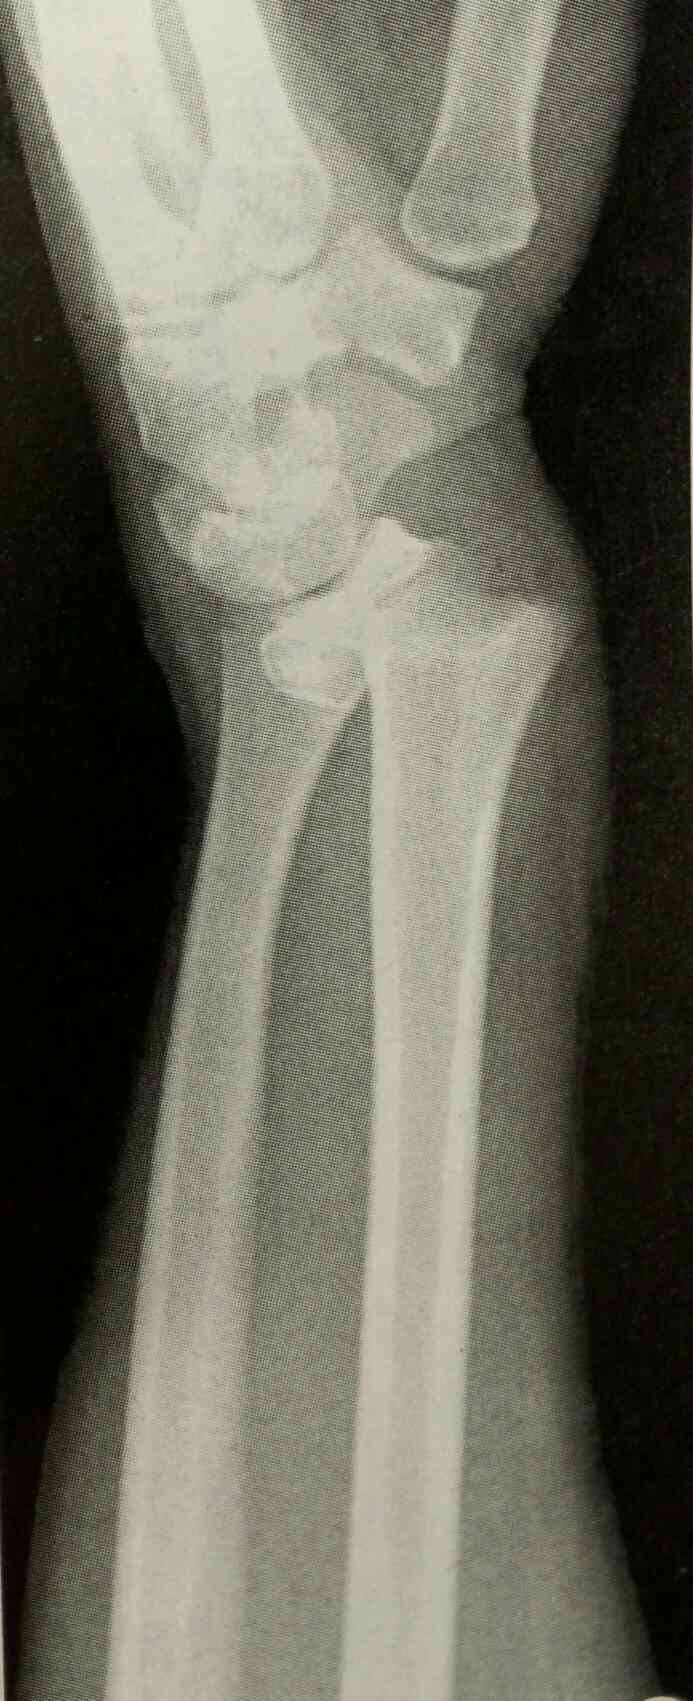

一般资料】 女性,65岁 【主诉】 因“发热伴恶心、呕吐、右上腹痛4d”入院。 【现病史】 4d前着凉后出现咽痛、发热,热时寒战,体温最高达39℃,伴有右上腹、胸背部及四肢关节疼痛,恶心、呕吐多次,进食水时明显,呕吐物为胃内容物,无咖啡样液体。无明显咳嗽、咳痰,无喘息、气短,无腹泻。于当地医院给予“抗感染及退热药”等治疗,症状无改善,为进一步诊治转入本院。患病以来精神、饮食、睡眠差,近4d未排便,有排气,排尿正常。 【既往史】 30年前曾患“胆囊炎”,自诉已治愈。4年前曾发现血糖升高,空腹8mmol/L左右,未系统诊治。半月前无明显诱因于背部、腹部及大腿皮肤出现红色皮疹,无瘙痒,未诊治。 【体格检查】 体温39.1℃,脉搏96次/min,呼吸22次/min,血压120/70 mmHg。神清,精神萎靡,全身皮肤无黄染及出血点,腹部、背部及大腿皮肤可见散在分布红色皮疹。浅表淋巴结无肿大,巩膜无黄染。口唇无紫绀,咽红,右侧扁桃体III0肿大,无脓苔,左侧扁桃体无明显肿大。听诊双肺呼吸音略粗,双肺未闻及干湿罗音。心界不大,心率96次/min,律齐。腹软,右上腹有压痛,无反跳痛及肌紧张,Murphy征阳性,肝脾肋下未触及,肠鸣音正常。双下肢无水肿。 【辅助检查】 9月16日急诊查肺CT:两肺下叶纹理增强,余未见异常。 腹部彩超提示:脂肪肝,脾胰及双肾未见明显占位性病变。 血常规:白细胞16.55×109/L,中性粒细胞84.5%。 入科后查心电图提示:窦性心律,T波改变。 血气分析正常;血钾2.6mmol/L。超敏反应蛋白121.94mg/L。 肝功能:白蛋白33.9g/L,白球比1.1,GGT68U/L,余正常。 肾功能:尿酸109.7μmol/L,随机血糖12.6mmol/L,糖化血红蛋白10.3%,血清碳酸氢盐测定20.9mmol/L,余正常。 心肌酶谱:乳酸脱氢酶255U/L,余正常。结核杆菌抗体测定阴性,肺炎支原体血清学试验阴性。免疫四项均正常。血清脂肪酶测定及血尿淀粉酶均正常。血沉49mm/H。 凝血四项:活化部分凝血酶原时间45.6s,血浆纤维蛋白原5.67g/L,凝血酶时间9.5s,余正常。血浆D-二聚体测定5.22μg/ml,纤维蛋白(原)降解产物12.2μg/ml。 尿常规:未见异常。 【诊断】 (1)急性胆囊炎?(2)低钾血症;(3)皮疹原因待查;(4)2型糖尿病;(5)成人Still病待除外。 【治疗】 给予抗感染、退热、补钾及对症治疗,完善相关检查。给予注射用头孢哌酮舒巴坦3.0g,静脉滴注2次/d,血必净注射液50ml,静脉续滴1次/d,注射用泮托拉唑钠40mg静脉续滴1次/d,枸橼酸钾颗粒2.92g,口服3次/d,以及补液、退热治疗。 患者入院第2天面部出现皮疹,伴有瘙痒。请皮肤科会诊,考虑为过敏性皮炎,给予卤米松乳膏15g外用;依巴斯汀片10mg,口服1次/d。停用注射用头孢哌酮钠他唑巴坦钠;给予盐酸莫西沙星氯化钠注射液0.4g,静脉滴注1次/d抗感染治疗。请消化科会诊,考虑胆囊炎诊断依据不足。患者仍有发热,体温最高39.4℃,畏寒,无寒战,恶心呕吐1次,为少量胃内容物,查体Murphy征阳性,临时给予双氯芬酸钠缓释片75mg口服及一般物理降温后患者体温逐渐降至正常。 入院第3天复查血细胞分析:白细胞22.3×109/L,中性粒细胞百分比81.9%,血红蛋白109g/L。风湿谱:超敏反应蛋白161mg/L,余正常。离子:钾3.3mmol/L,钠、氯正常。心肌酶谱:乳酸脱氢酶262U/L,余正常。肾功能:尿酸137μmol/L,空腹血糖12.7mmol/L,余正常。早餐后2h血糖15.5mmol/L,患者空腹及餐后血糖高,请内分泌科会诊,诊断:2型糖尿病。给予控制饮食及盐酸二甲双胍500mg,口服,3次/d,监测血糖。复查肝胆脾彩超回报:脂肪肝,胆囊壁强回声(胆固醇结晶?);血清铁蛋白测定>2000.00ng/ml。降钙素原0.193ng/ml。免疫球蛋白:免疫球蛋白G12.31g/L,免疫球蛋白A2.62g/L,免疫球蛋白M0.76g/L,补体C31.13g/L,补体C40.27g/L。甲功三项:游离三碘甲状腺原氨酸1.53pg/ml,余正常。心钠素(发光法)201.89pg/ml。抗核抗体谱及脉管炎自身抗体均阴性。血培养阴性。请风湿免疫科会诊,考虑成人Still病可能性大,建议转科治疗。转科后给予非甾体抗炎药及糖皮质激素等治疗,病情稳定后出院。